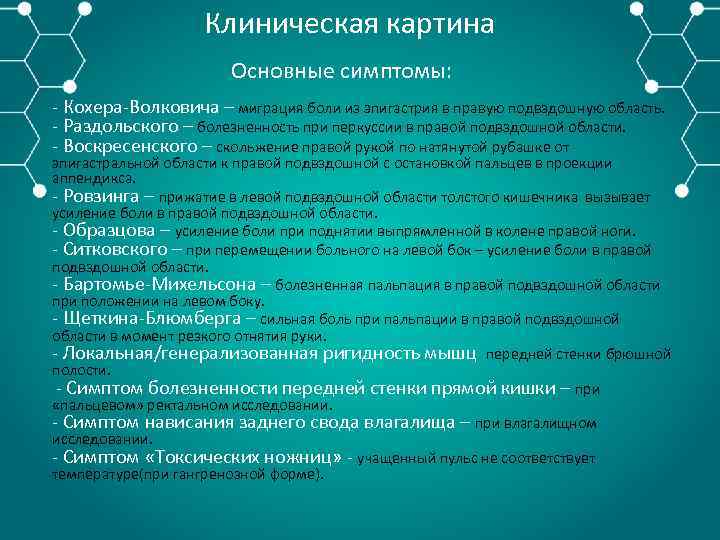

Клиническая картина Основные симптомы: Кохера Волковича – миграция боли из эпигастрия в правую подвздошную область. Раздольского – болезненность при перкуссии в правой подвздошной области. Воскресенского – скольжение правой рукой по натянутой рубашке от эпигастральной области к правой подвздошной с остановкой пальцев в проекции аппендикса. Ровзинга – прижатие в левой подвздошной области толстого кишечника вызывает усиление боли в правой подвздошной области. Образцова – усиление боли при поднятии выпрямленной в колене правой ноги. Ситковского – при перемещении больного на левой бок – усиление боли в правой подвздошной области. Бартомье Михельсона – болезненная пальпация в правой подвздошной области при положении на левом боку. Щеткина Блюмберга – сильная боль при пальпации в правой подвздошной области в момент резкого отнятия руки. Локальная/генерализованная ригидность мышц передней стенки брюшной полости. Симптом болезненности передней стенки прямой кишки – при «пальцевом» ректальном исследовании. Симптом нависания заднего свода влагалища – при влагалищном исследовании. Симптом «Токсических ножниц» учащенный пульс не соответствует температуре(при гангренозной форме).